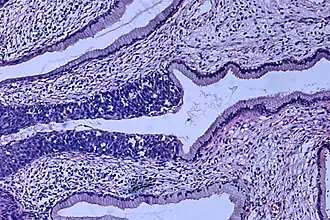

Cancer de col uterin

Cancerul de col uterin este un neoplasm malign al colului uterin sau cervixului cum mai este numit. Se poate manifesta prin sângerare vaginală, dar simptomele sunt de multe ori absente până când cancerul e deja într-un stadiu avansat. Tratamentul constă în intervenție chirurgicală (incluzând excizie locală) în stadiile incipiente și chimioterapie împreună cu radioterapie în stadiile avansate ale bolii.